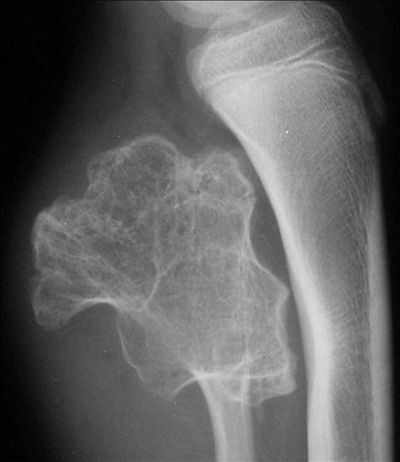

腓骨骨软骨瘤-X线

【普通放射图片】:

腓骨骨软骨瘤-普通放射病例影像诊断

【影像表现】:X线平片示腓骨近端骨软骨瘤,肿瘤基底部的骨皮质与小梁均与母体骨相连续。

【影像诊断】:腓骨骨软骨瘤。